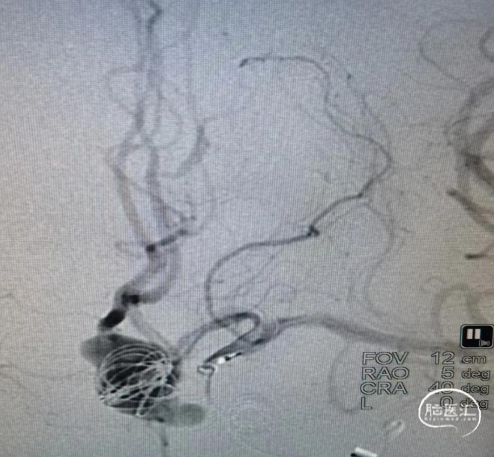

CTA:见前交通动脉瘤,大脑前动脉共干,动脉瘤16*10*9大小,双侧A2均由动脉瘤上发出,右侧A2开口呈180°回旋。

术前造影显示大脑前动脉瘤。